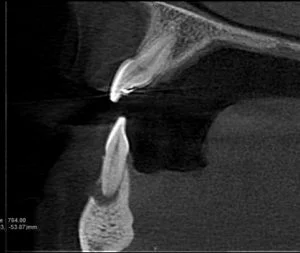

A CBCT was taken after a negative cold test indicated a necrotic tooth.  When the CBCT was taken, we could clearly see that the abscess had completely perforated the labial bone at the apex of #24 and was close to doing so on #25.

As we investigated more deeply, we identified another critical piece of information that would affect our treatment plan: a second canal on #24.